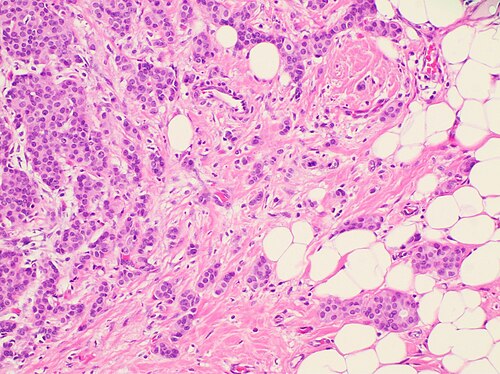

An 80-year-old woman presents with fatigue and a 30-lb weight loss over the past 3 months. The patient states that her symptoms started with mild fatigue about 4 months ago, which have progressively worsened. She noticed that the weight loss started about 1 month later, which has continued despite no changes in diet or activity level. The past medical history is significant for a total abdominal hysterectomy (TAH), and bilateral salpingo-oophorectomy at age 55 for stage 1 endometrial cancer. The patient takes no current medications but remembers taking oral (estrogen/progesterone) contraceptives for many years. The menarche occurred at age 10, and the menopause was at age 50. There is no significant family history. The vital signs include: temperature 37.0℃ (98.6℉), blood pressure 120/75 mm Hg, pulse 97/min, respiratory rate 17/min, and oxygen saturation 98% on room air. The physical examination is significant for a palpable mass in the upper outer quadrant of the left breast. The mass is hard and fixed with associated axillary lymphadenopathy. The mammography of the left breast shows a spiculated mass in the upper outer quadrant. An excisional biopsy of the mass is performed, and the histologic examination reveals the following significant findings (see image). Immunohistochemistry reveals that the cells from the biopsy are estrogen receptor (ER)/progesterone receptor (PR) and human epidermal growth factor receptor-2 (HER-2)/neu positive. Which of the following is the most important indicator of a poor prognosis for this patient?